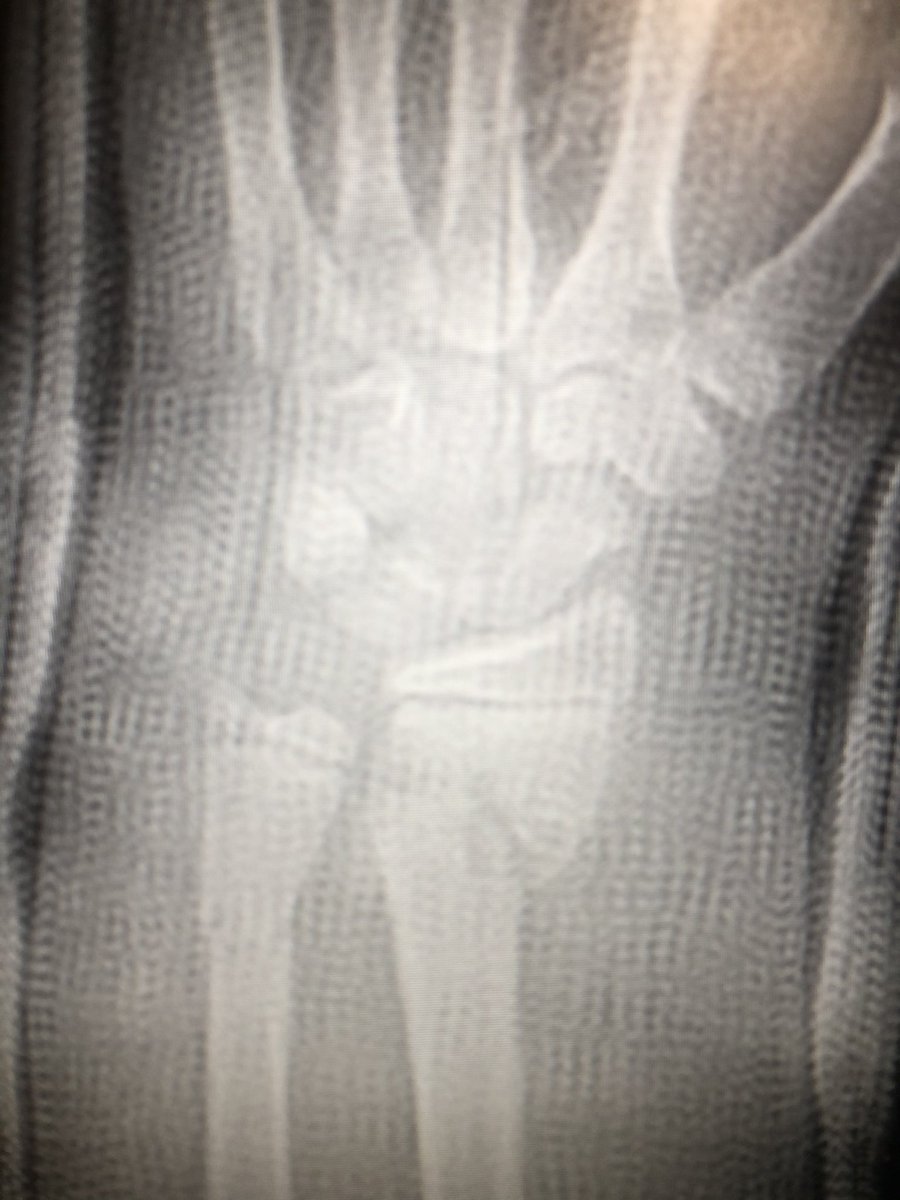

[4/4] I didn’t I think one wire was going to be enough, so I removed joystick and then placed another smooth wire proximal to distal; there wasn’t much room in there because trying not to get the physis. Cast, then pins pulled in clinic at 4 weeks. Xrays done at 2, 4, 8 weeks.